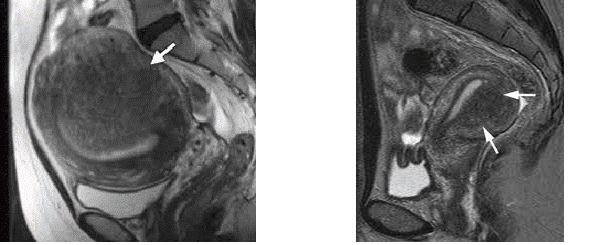

Bij een MRI wordt er een beeld gemaakt van de hele buik. Hiervoor moet een aparte afspraak gemaakt worden bij de afdeling Radiologie. De MRI-scan wordt ook beoordeeld door de radioloog. Het kan dus niet direct door de gynaecoloog zelf in de spreekkamer worden gedaan. Ook bij een MRI is het belangrijk dat de radioloog bekend is met de kenmerken van endometriose voor het vaststellen of uitsluiten van endometriose.

MRI van radioloog met kennis van adenomyosis of endometriosis interna